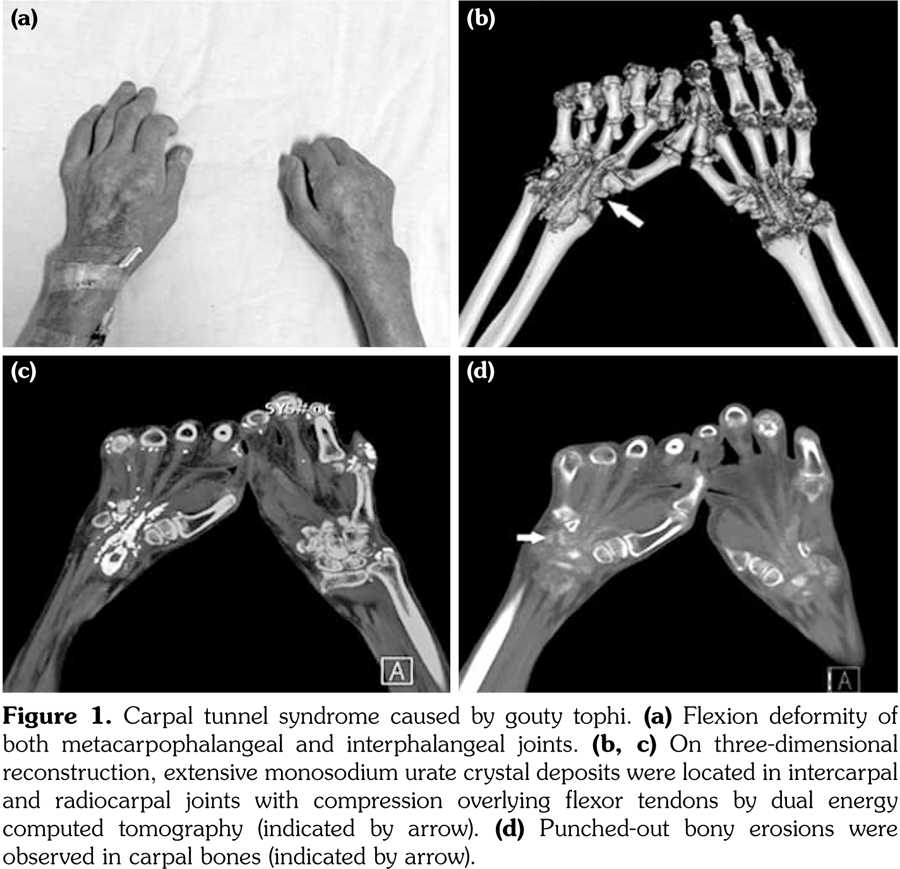

A 54-year-old male patient was admitted to our department with palmar numbness and disability for two years. He had a history of gout for 30 years but received no treatment. Physical examination revealed obvious subcutaneous tophi and thenar muscle wasting. Flexion deformity of his metacarpophalangeal and interphalangeal joints is shown in Figure 1a. Positive Tinel’s sign and Phalen’s maneuver were present. Routine laboratory test showed high level of uric acid (608 μmol/L). The electrophysiological examination revealed sensory and motoring demyelinating and axon lesions in both median nerve, especially in the right hand, which supported the diagnosis of CTS. Furthermore, DECT showed extensive monosodium urate crystals in the intercarpal and radiocarpal joints with compression overlying the flexor tendons (Figure 1b, c). We also observed punched-out bony erosions in the carpal bones (Figure 1d). These aspects indicated severe and typical CTS caused by gouty tophi, which was further confirmed by biopsy of fine-needle aspiration (Figure 2). Surgery was recommended, but the patient refused to undergo surgery and chose to receive febuxostat. Uric acid level had decreased in the next six-month follow-up with little improvement for his numbness and deformity. A written informed consent was obtained from the patient.